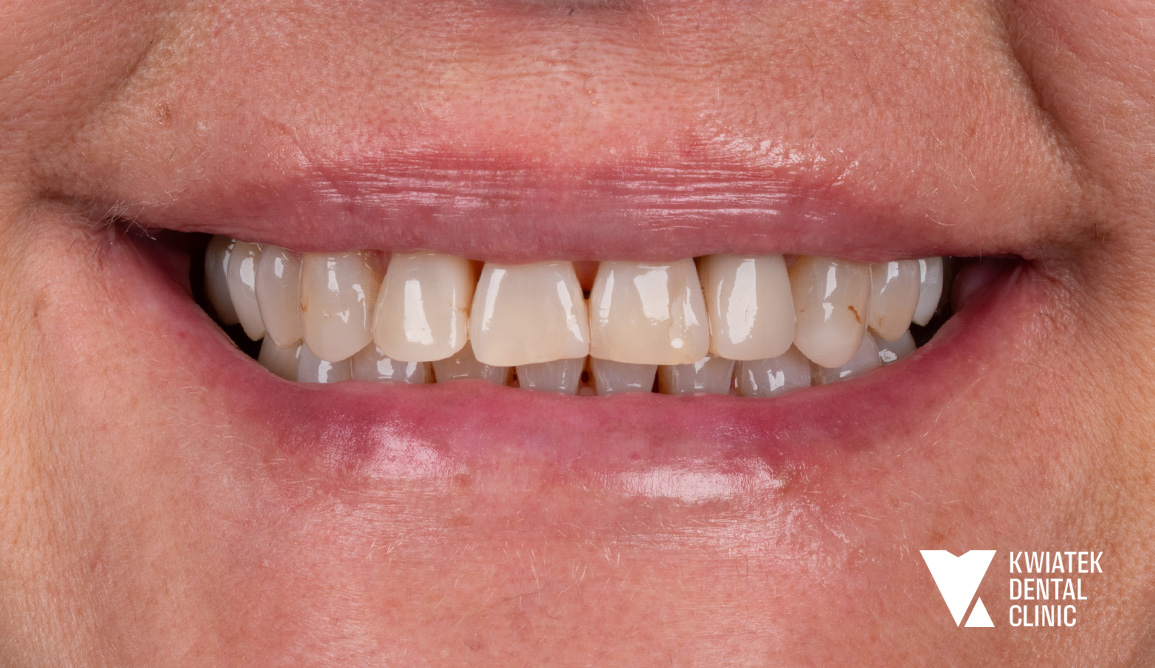

Kobieca harmonia - naturalna metamorfoza pełna światła i finezji

Pani Hanna zgłosiła się z uśmiechem naznaczonym wieloletnimi wypełnieniami, przebytym leczeniem ortodontycznym oraz zaburzoną funkcją zgryzu. Po kompleksowej diagnostyce, starannym przygotowaniu tkanek i profesjonalnym wybielaniu wykonano precyzyjny remodeling zębów metodą flow injection, który przywrócił naturalne proporcje, świetlistość i harmonię łuków zębowych. Rezultatem jest metamorfoza subtelna, a zarazem wyraźnie odmieniająca wyraz twarzy, uśmiech jasny, elegancki i w pełni naturalny, podkreślający kobiecą delikatność oraz ponadczasową estetykę.